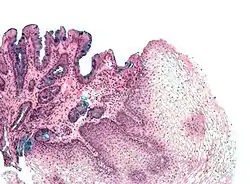

Both macroscopic (from endoscopy) and microscopic positive findings are required to make a diagnosis. Barrett's esophagus is marked by the presence of columnar epithelia in the lower esophagus, replacing the normal squamous cell epithelium—an example of metaplasia. The secretory columnar epithelium may be more able to withstand the erosive action of the gastric secretions; however, this metaplasia confers an increased risk of adenocarcinoma.[17]

Intestinal metaplasia

The presence of goblet cells, called intestinal metaplasia, is necessary to make a diagnosis of Barrett's esophagus. This frequently occurs in the presence of other metaplastic columnar cells, but only the presence of goblet cells is diagnostic. The metaplasia is grossly visible through a gastroscope, but biopsy specimens must be examined under a microscope to determine whether cells are gastric or colonic in nature. Colonic metaplasia is usually identified by finding goblet cells in the epithelium and is necessary for the true diagnosis.[25]

Many histologic mimics of Barrett's esophagus are known (i.e. goblet cells occurring in the transitional epithelium of normal esophageal submucosal gland ducts, "pseudogoblet cells" in which abundant foveolar [gastric] type mucin simulates the acid mucin true goblet cells). Assessment of relationship to submucosal glands and transitional-type epithelium with examination of multiple levels through the tissue may allow the pathologist to reliably distinguish between goblet cells of submucosal gland ducts and true Barrett's esophagus (specialized columnar metaplasia). The histochemical stain Alcian blue pH 2.5 is also frequently used to distinguish true intestinal-type mucins from their histologic mimics. Recently, immunohistochemical analysis with antibodies to CDX-2 (specific for mid and hindgut intestinal derivation) has also been used to identify true intestinal-type metaplastic cells. The protein AGR2 is elevated in Barrett's esophagus[26] and can be used as a biomarker for distinguishing Barrett epithelium from normal esophageal epithelium.[27]

The presence of intestinal metaplasia in Barrett's esophagus represents a marker for the progression of metaplasia towards dysplasia and eventually adenocarcinoma. This factor combined with two different immunohistochemical expression of p53, Her2 and p16 leads to two different genetic pathways that likely progress to dysplasia in Barrett's esophagus.[28] Also intestinal metaplastic cells can be positive for CK 7+/CK20−.[29]